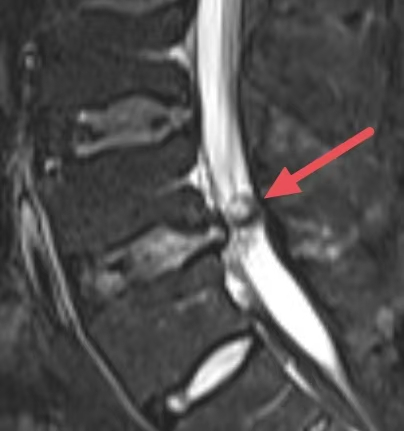

(磁共振影像下的腰椎间盘脱出所见)

磁共振技术被誉为软组织的“透视眼”。磁共振利用水分子振动成像,对椎间盘、脊髓、神经根、韧带等含水量高的软组织具有极高的分辨率。在磁共振图像上,医生可以清晰地看到突出的椎间盘究竟在哪个位置、压迫了哪一根神经根、压迫的程度是轻度接触还是重度挤压,甚至能观察到神经本身是否出现了水肿或变性。

罗某,男,47岁,因“反复腰背部左臂、左大腿疼痛1周,加重1天”入院,MR(磁共振)检查显示:L4/5椎盘膨出并左后突出,腰椎骨质增生。经专家团队讨论征求家属同意后成功开展“脊柱内镜下腰椎间盘髓核摘除术”,一周后康复出院。

(腰2骨折伴相应水平椎管内肿瘤MR及显微镜下所见)

魏某,男,48岁,“上楼梯时不慎摔伤”致腰部疼痛、活动受限入院,MR(磁共振)检查显示:L2椎体骨折,腰2水平椎管内占位性病变。经外三科(神经外科、脊椎外科)主任、副主任医师吴隆俊团队讨论并经家属同意后一期行:显微镜下椎管内病损切除术 腰椎骨折内固定术。术后恢复良好,避免患者多次手术。